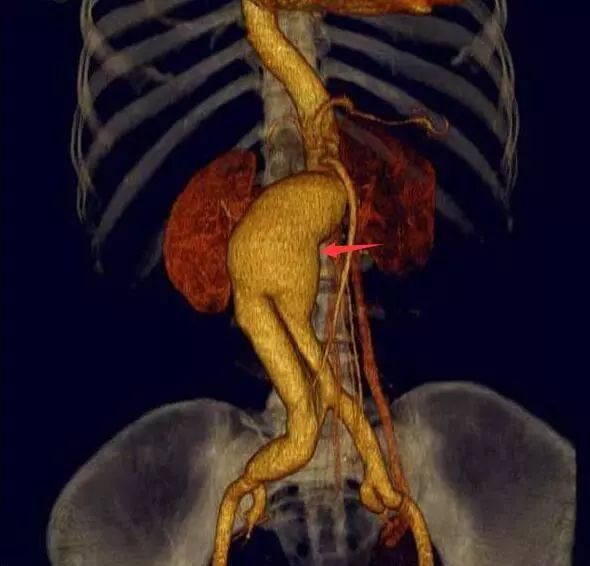

腹主動脈CTA圖像

患者動脈瘤呈梭形